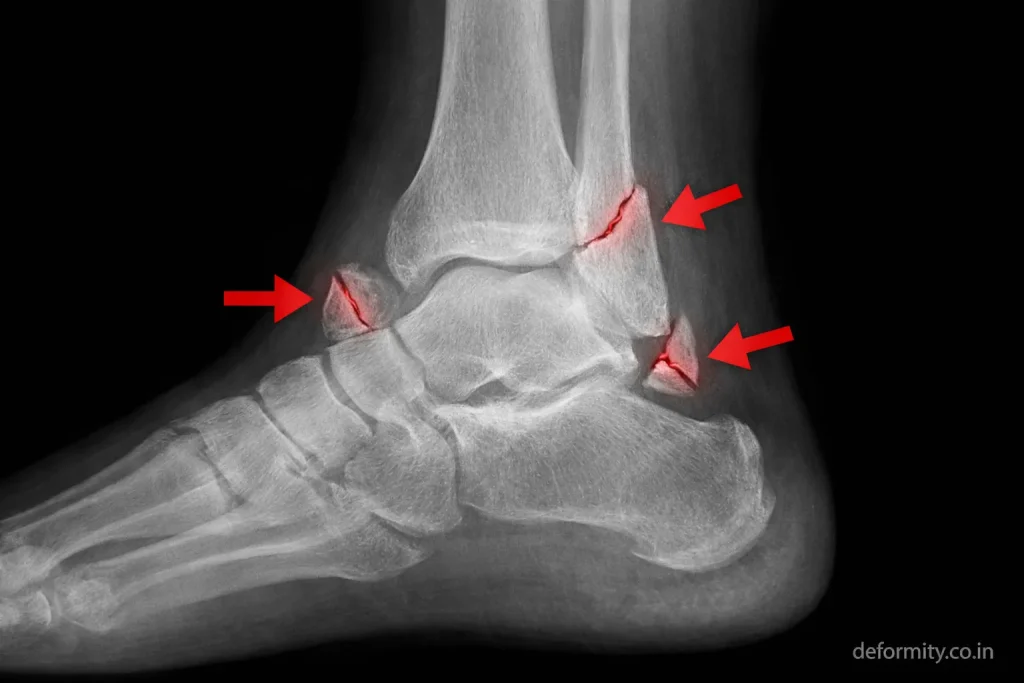

Trimalleolar Fracture Radiology

Radiology plays a critical role in diagnosis and surgical planning.

X-ray Findings

Standard X-ray views include:

- AP view

- Lateral view

- Mortise view

Findings may show:

- Fracture lines on the medial and lateral sides

- Posterior malleolus fragment on lateral view

- Joint misalignment

- Talar shift

Radiology Features of Instability

Radiological signs of instability include:

- Syndesmotic widening

- Medial clear space widening

- Talar displacement

- Posterior fragment displacement

Detailed radiological evaluation ensures accurate treatment planning.